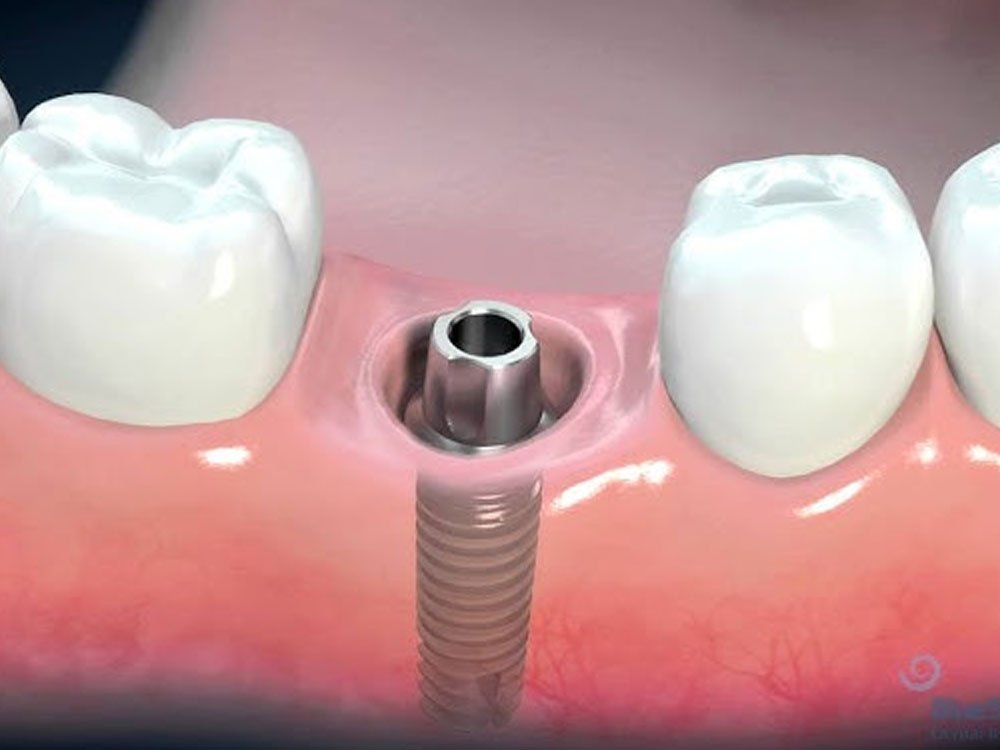

Dental implants are artificial tooth roots made of biocompatible materials like titanium. They are surgically inserted into the jawbone to support replacement teeth such as crowns, bridges, or dentures. Implants provide a strong foundation and feel, function, and look like natural teeth.

Conventional implants are the most commonly used type of implant worldwide. These implants require sufficient bone volume and density for placement. In cases of bone loss, patients may need bone grafting procedures before receiving conventional implants.